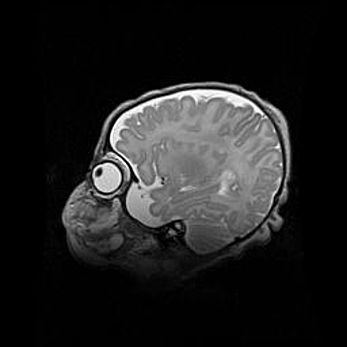

Лейкомаляция с кистозно-глиозной дегенерацией головного мозга.

Возраст: 2 месяца 25 дней

Вес: 6400 г

Окружность головы: 40 см

Срок гестации: 41 неделя

Лейкомаляцию относят к ишемически-гипоксическим повреждениям головного мозга, диагностируемым у новорожденных. При лейкомаляции в головном мозге обнаруживают очаги некроза, возникшие после тяжелой гипоксии и нарушения кровотока. В процессе морфогенеза очаги проходят три стадии: 1) развития некроза, 2) резорбции и 3) формирования глиозного рубца или кисты. Перивентрикулярная лейкомаляция (ПЛ) встречается примерно в 12% случаев среди новорожденных, обычно – у недоношенных детей, причем, частота ее зависит от массы, с которой младенец появился на свет. Наибольшее число малышей страдает лейкомаляцией, если масса при рождении 1500-2500 г.